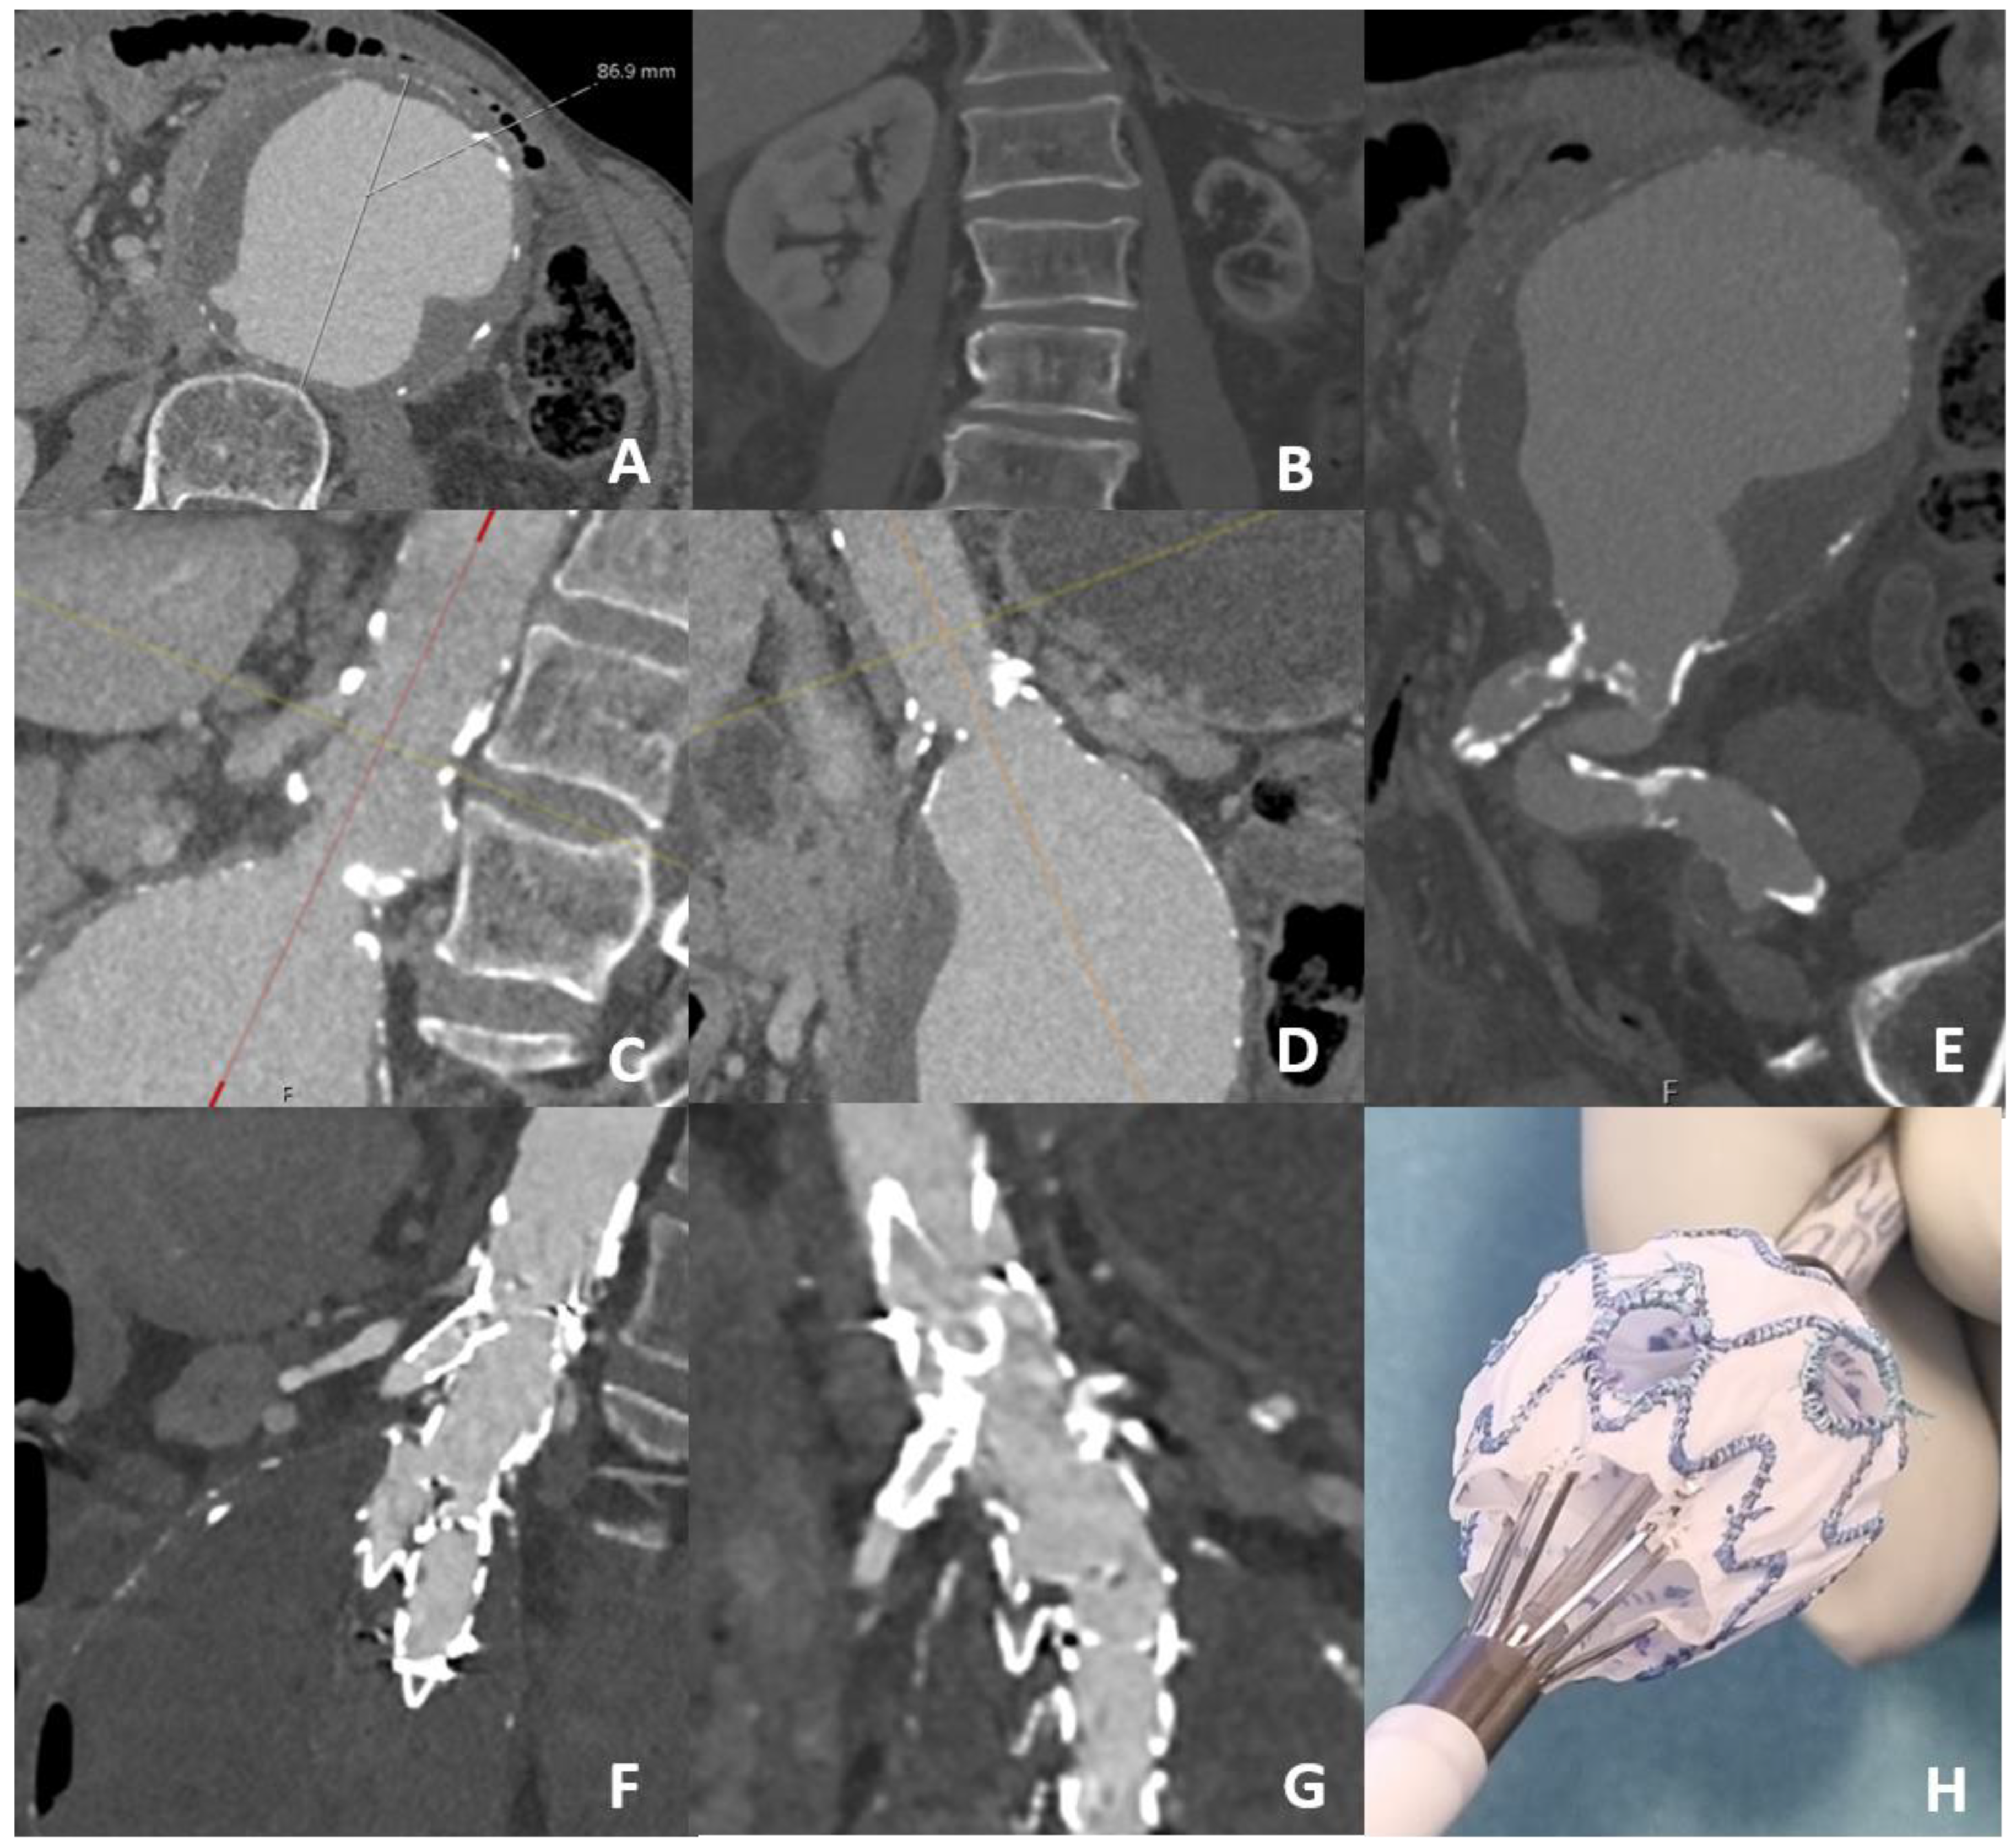

| Aneurysm diameter | 64.0 ± 17.8 |

| Infrarenal neck length | 8.0 ± 5.5 |

| Proximal landing zone a | 26.9 ± 10.7 |

| Gained landing zone through pm-fenestrations b | 18.9 ± 11.4 |